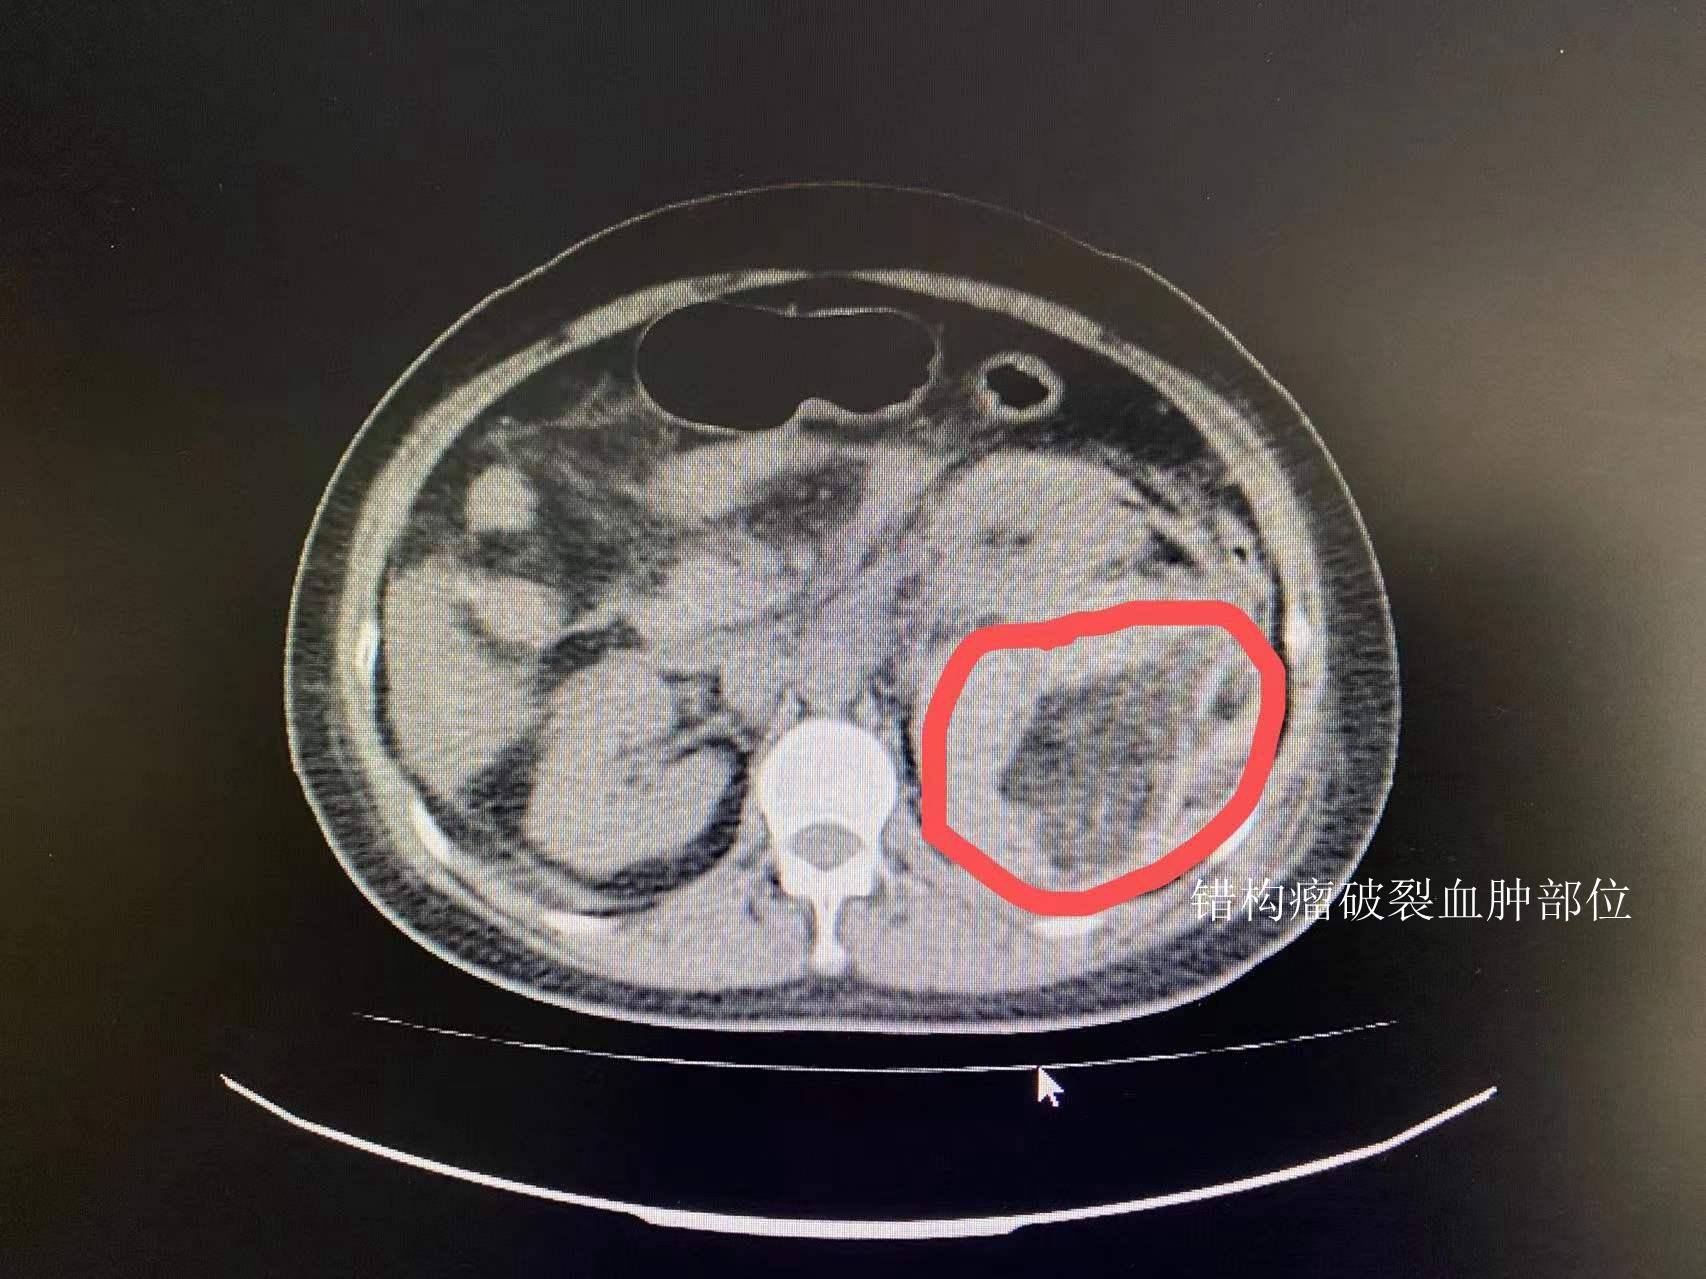

当地医院就诊,经ct检查发现李女士左肾出血,考虑为左肾错构瘤破裂出血

巨大左肾错构瘤自发性破裂出血1例 - 好大夫在线